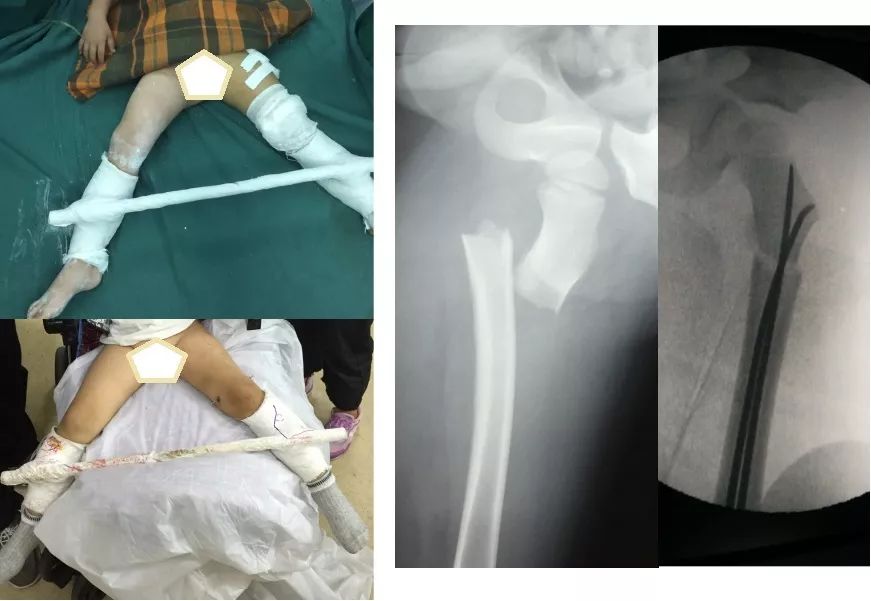

此处应用钢板有两种情况一是不会使用髓内固定,设备条件达不到;再就是理念落后见的病例少,交流少。此处外侧全部是长应力,钢板为张力钢板,内收肌力量强大,目前的钢板不能承受反复的弯曲应力,金属疲劳断裂失败率高,以下病例切开,钢丝捆绑进一步骨膜剥离,破坏了原始血肿,干扰骨愈合,都是失败原因

补救办法:剥削植骨髓内钉固定或动力髁钢板固定。

补救比较好